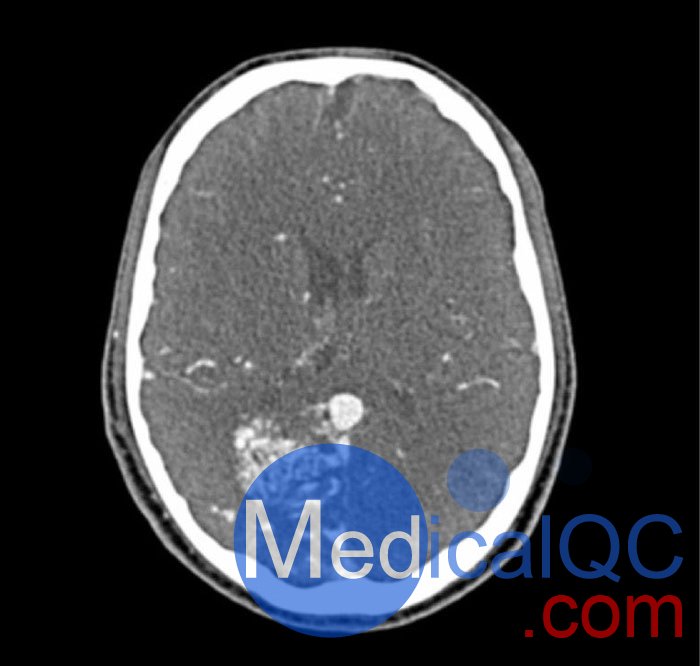

WEK-5005腦血管造影頭模,WEK-5005頭模, CTA AVM頭模模擬動脈期造影劑增強頭部(CT 血管造影)。 它覆蓋枕骨大孔的頂點。

該模型在半卵圓中心有 10 個低對比度病變,右半球有動靜脈畸形。

WEK-5005腦血管造影頭模,WEK-5005頭模, CTA AVM頭模成像效果圖:

WEK-5005腦血管造影頭模,WEK-5005頭模, CTA AVM頭模成像效果圖